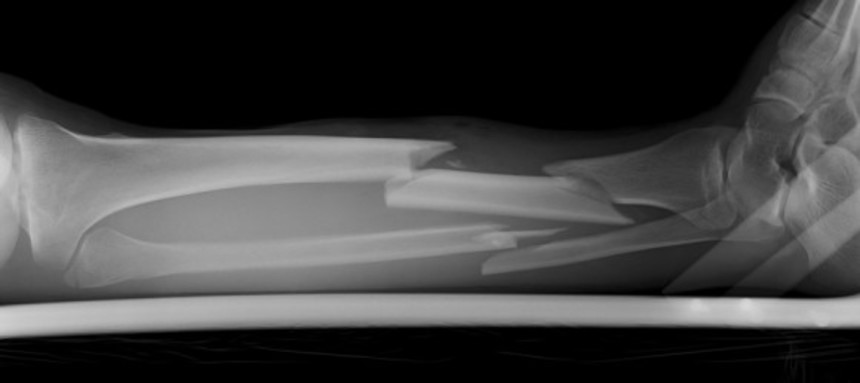

全員、通常わたしたちが感じるような痛みを感じる感覚がほとんどなく、怪我をしても気がつかない。手足を骨折しても、痛くないので気がつかないのだ。

78歳のドメーニカはこれまで何度も骨折しているが、レントゲン撮影の結果、それに気が付くことなく自然に硬化していることがわかった。また火傷も平気なので皮膚には火傷の跡が数多く残されている。

ドメーニカの娘、レティツィア(52)はスキーで肩を骨折たが、その後もスキーを続け、運転して家に帰ってきたという。翌日になるまで自分が骨折したことに気づかなかったという。テニスをして、肘の骨を折ったときも同様だった。

レティツィアの息子、ルドヴィコ(24)はサッカーをやっているのだが足首にいくつも骨折の跡がみられた。次男のベルナルド(21)は自転車から転倒しやはり骨折していたのだが気が付かず、肘に骨折の跡があったという。